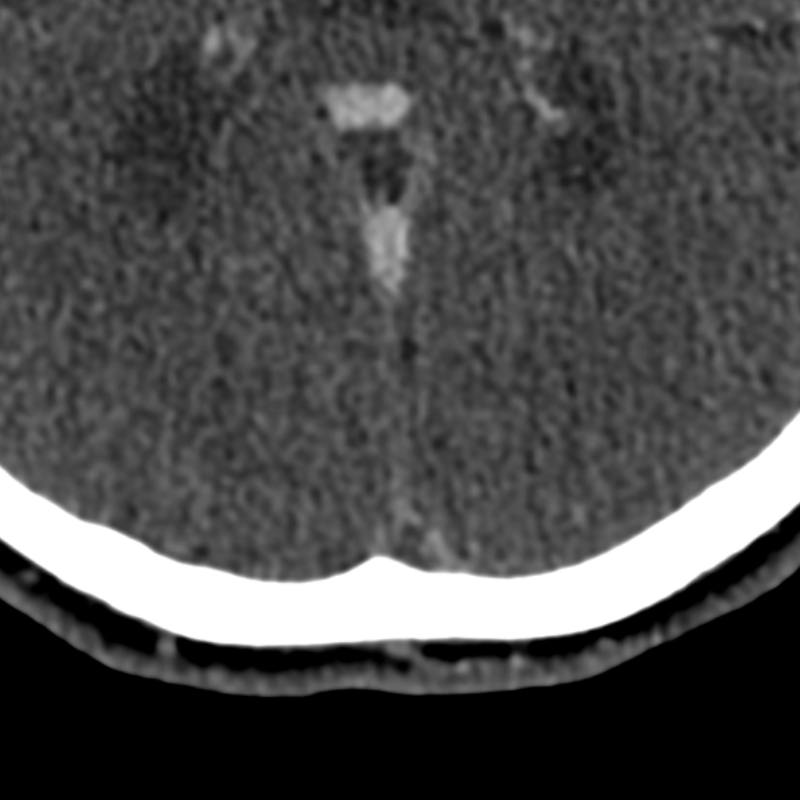

- 65-year-old patient on treatment for metastatic lung cancer.

- CT showed hyperdensity in the straight sinus, vein of Galen and internal cerebral veins.

- These vessels did not enhance on the CTV.

- MRI the next day showed hyperintensity and swelling of the deep grey structures and the capsular white matter.